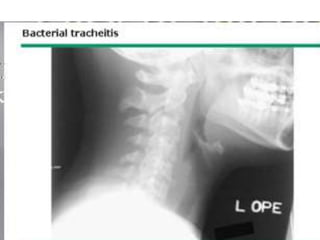

BACTERIAL TRACHEITIS

(PSEUDOMEMBRANOUS CROUP

• Bacterial tracheitis is a rare but important

cause of severe upper airway obstruction and

should be considered in older patients with

stridor or in infants who do not respond to

racemic epinephrine inhalation.

• Children with this condition initially have

symptoms that are similar to epiglottitis or

severe viral laryngotracheitis

• Lateral neck radiographs show subglottic narrowing and

foreign material in the tracheal lumen.

• Endoscopy reveals extensive sloughing of the respiratory

epithelium and large amounts of mucopurulent secretions

and debris blocking the trachea.

• These secretions may be difficult to remove and

progressively occlude the airway.

• Staphylococcus aureus is the most common organism that

is associated with this condition;

• nontypable H. influenzae, Branhamella catarrhalis, and

Streptococcus pneumoniae are less often the cause

• Treatment includes culture of secretions,

• appropriate intravenous antibiotics,

• oxygen,

• avoidance of fluid overload,

• and endotracheal intubation if there are signs

of progressive respiratory failure.